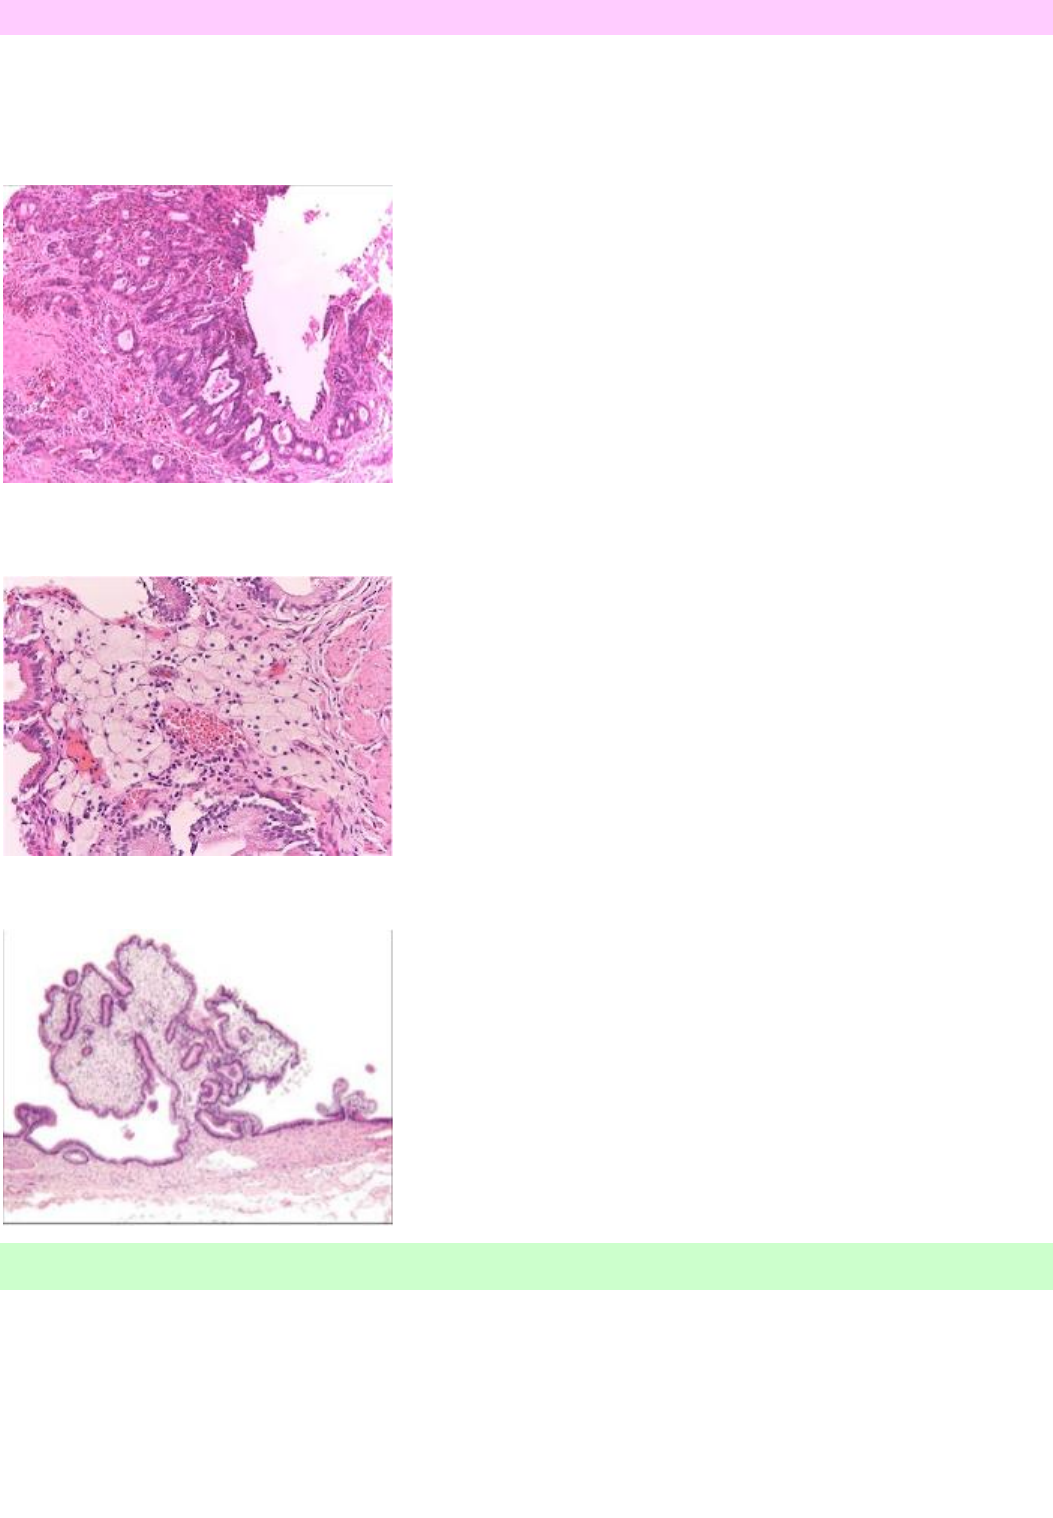

Observe a imagem abaixo referente ao exame anatomopatológico de uma vesícula biliar.

A) Trata-se de uma colicistite crônica onde são observados os seios de Rokitansky-Aschoff

B) Trata-se de um adenocarcinoma de vesícula biliar pouco diferenciado invadindo a serosa do órgão

C) Trata-se de uma colecistite aguda onde é observado dilatação de glândulas vesiculares e infiltrado neutrofílico

4- Observe a imagem abaixo referente ao exame anatomopatológico de uma vesícula biliar e assinale a

alternativa correta

C) Trata-se de uma colecistite aguda onde é observado dilatação de glândulas vesiculares e infiltrado

neutrofílico